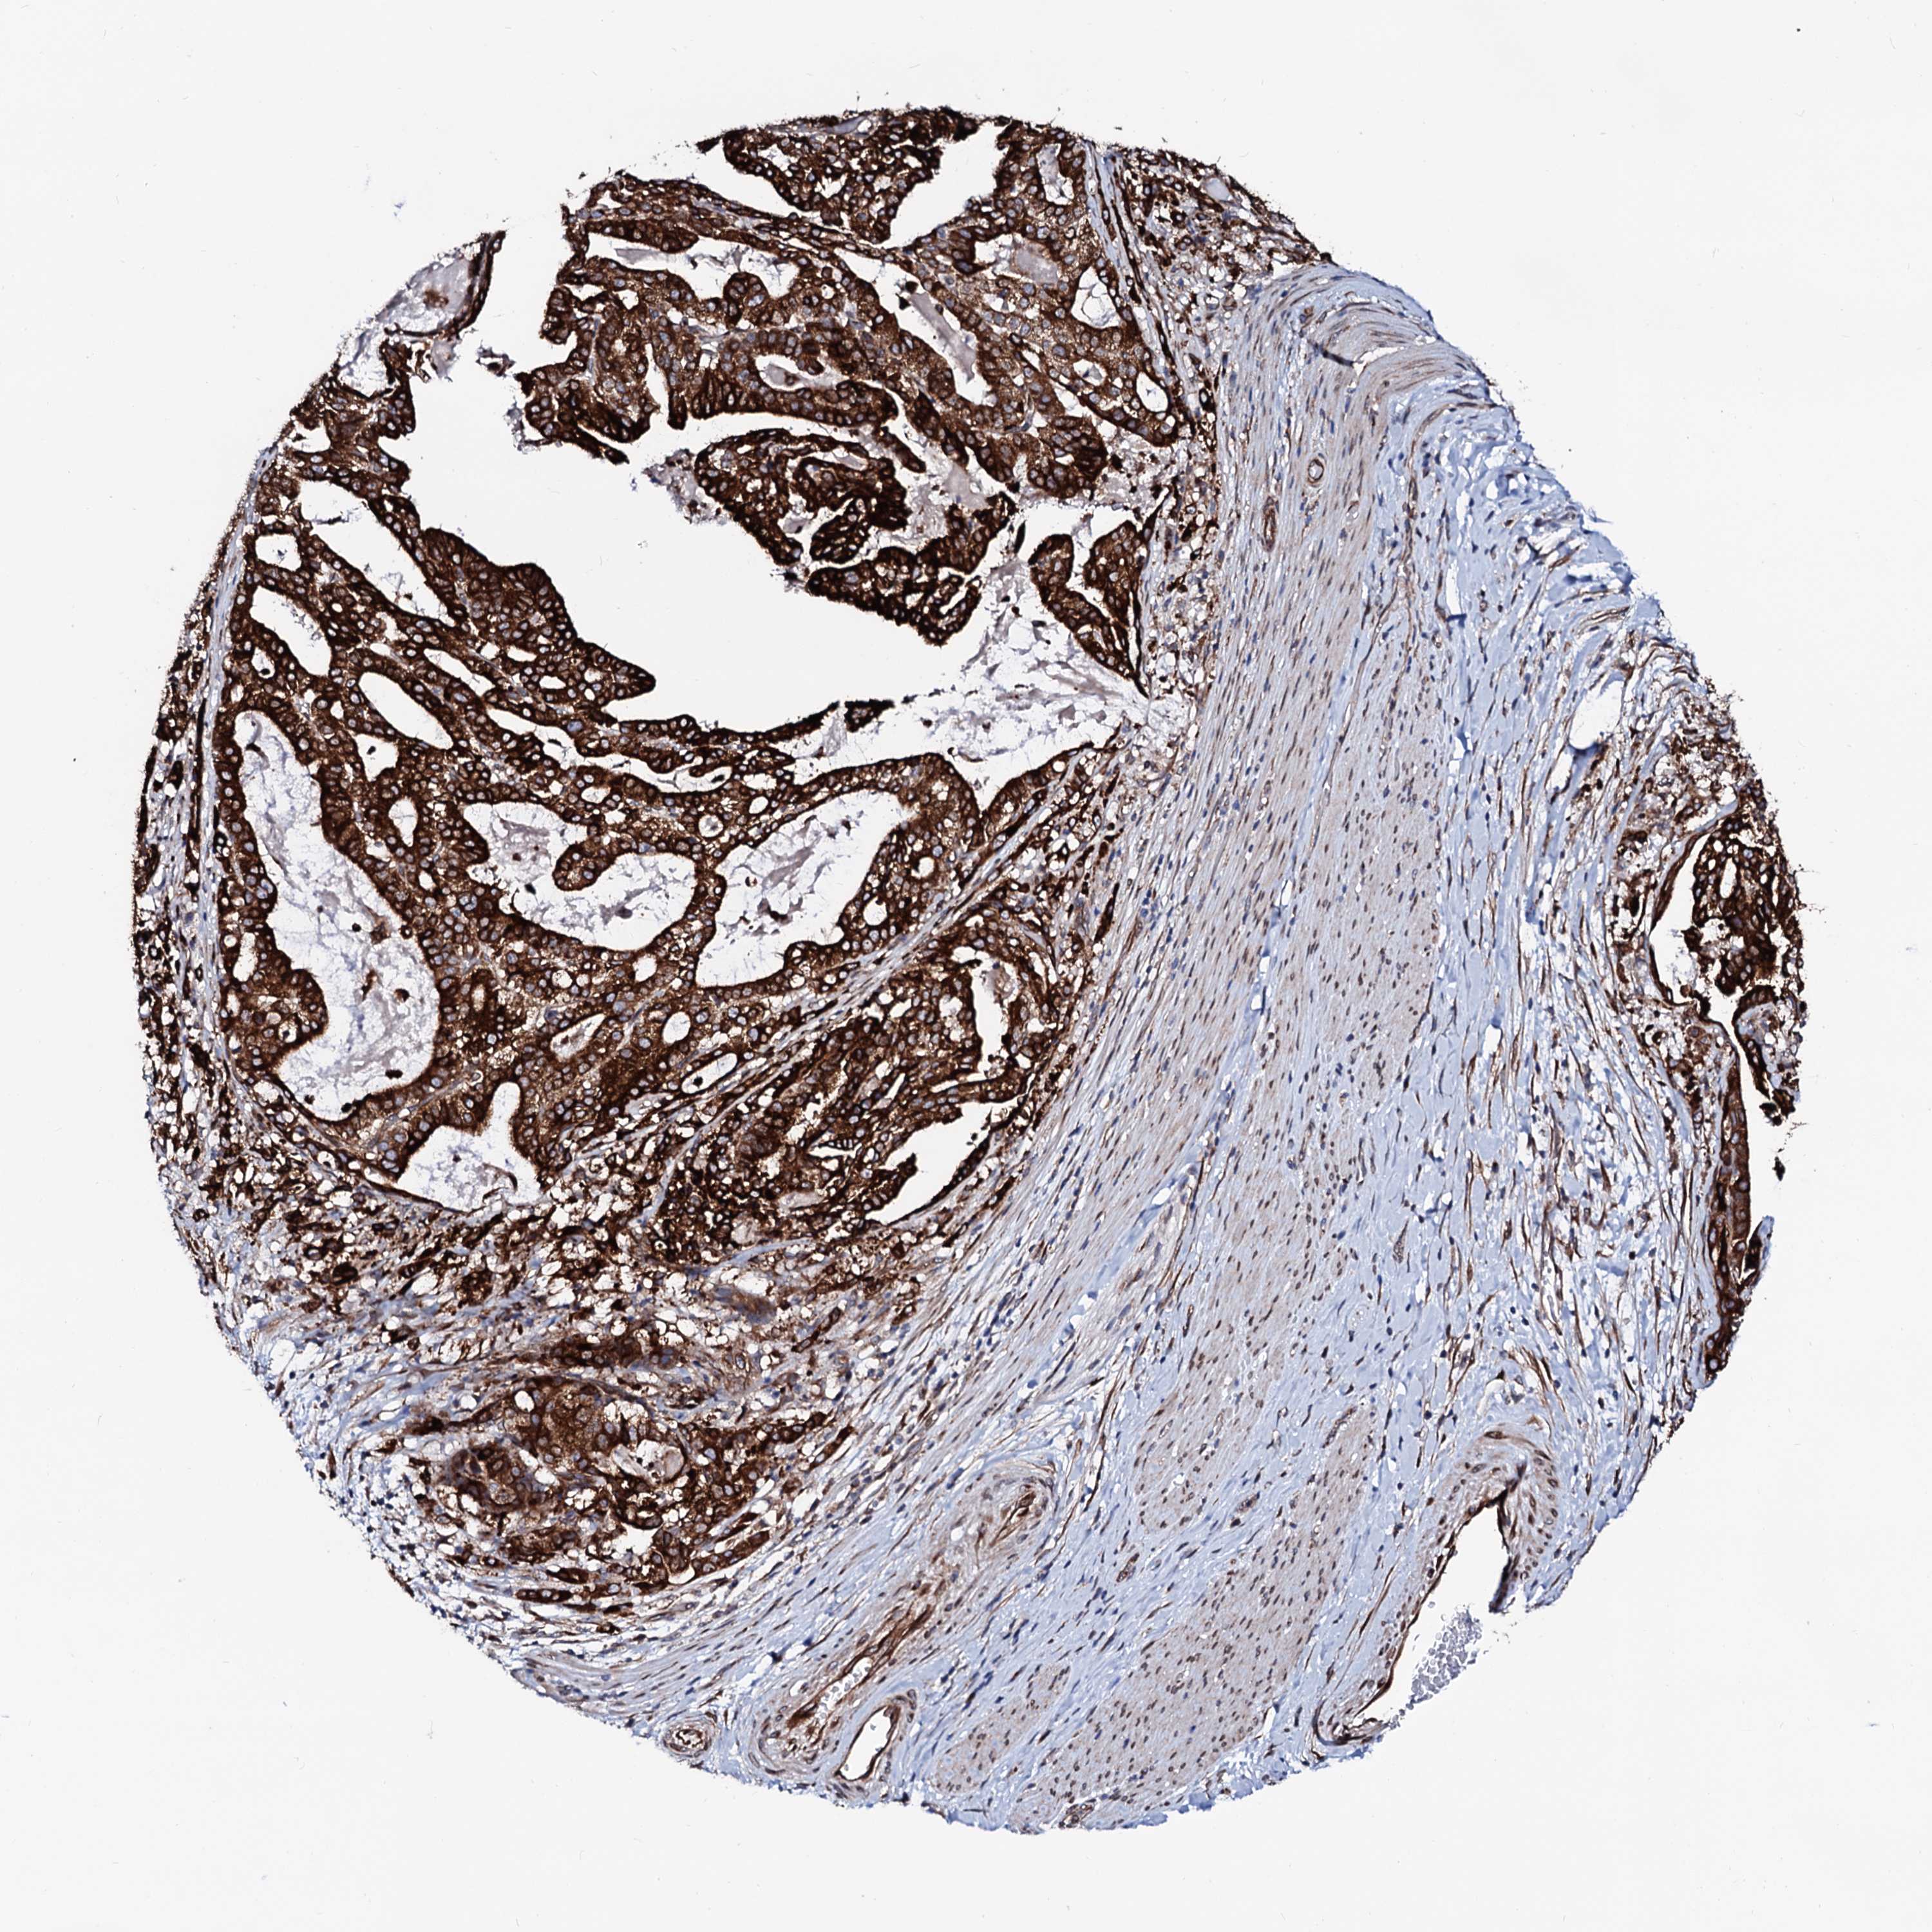

STOMACH CANCER - Protein expressioni

A mouse-over function shows sample information and annotation data. Click on an image to view it in a full screen mode. Samples can be filtered based on level of antibody staining by selecting one or several of the following categories: high, medium, low and not detected. The assay and annotation is described here.

Antibody stainingi

Antibody staining in the annotated cell types in the current human tissue is reported as not detected, low, medium, or high, based on conventional immunohistochemistry profiling in selected tissues. This score is based on the combination of the staining intensity and fraction of stained cells.

Each image is clickable and will lead to virtual microscopy that enables deeper exploration of all samples and also displays staining intensity scores, fraction scores and subcellular localization as well as patient and tissue information for each sample.

Antibody HPA039561

Antibody HPA048126

Staining

High

Medium

Low

Not detected

Intensity

Strong

Moderate

Weak

Negative

Quantity

>75%

75%-25%

<25%

None

Location

Nuclear

Cytoplasmic/membranous

Cytoplasmic/membranous,nuclear

Adenocarcinoma, NOS